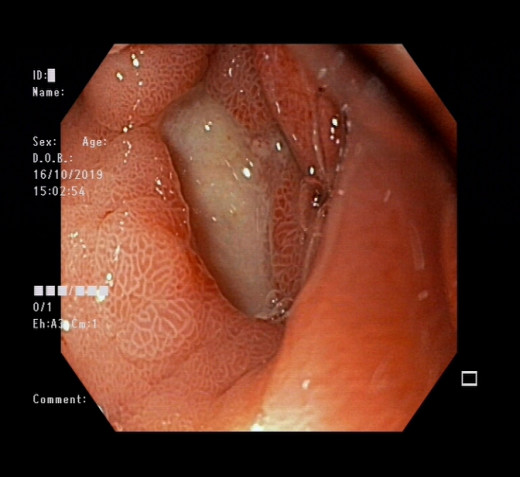

病例:消化性溃疡

患者:余**    性别:男    年龄:68岁     因“腹部疼痛伴恶心、呕吐1天”于2019年10月14日入院,并在我院行胃镜检查显示:胃窦溃疡。

行胃镜检查显示:胃窦溃疡

确诊后,我院消化内科团队开始针对患者情况进行治疗,症状明显得到缓解,无腹痛。

家礼医院消化内科团队提醒:胃溃疡是消化科最常见疾病,发病时患者以上腹部疼痛为主要症状,常呈隐痛、钝痛、胀痛、烧灼样疼痛。胃溃疡多发反复发作、瘢痕形成易形成幽门梗阻,导致食物不能消化,溃疡长期不愈合,特别是年龄45岁以上者有癌变风险。

胃溃疡并发症:消化道出血、癌变、梗阻、胃穿孔。

诊断方式:胃镜是诊断本病有效检查。